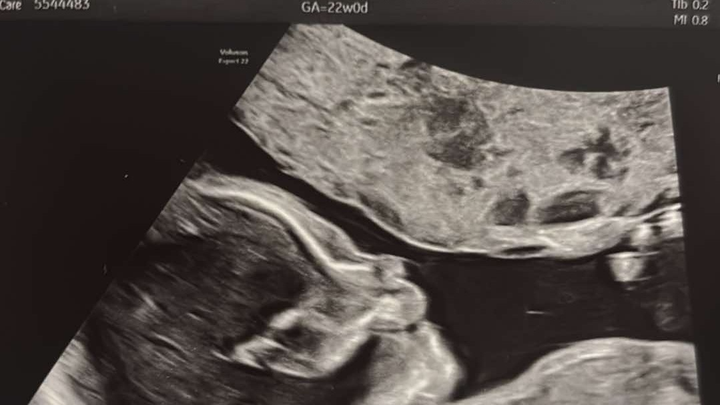

My name is Serenity I want to thank you for reading my unborn daughter's story. I’m 22 weeks pregnant currently, and our precious, miracle baby needs specialized care.

We are expecting baby #5, Brayleigh. We just spent the last few nights at St. Vincent Women’s High-Risk Unit. Brayleigh's right atrium of her heart is enlarged due to part of her tricuspid valve being stuck open. This causes her blood to go the wrong way, causing not enough blood to get to her lungs and not enough oxygenated blood getting to the rest of her body. I also have what they call placenta previa, which is where the placenta is covering the cervix, causing it to be high risk.

I will be hospitalized in 5 weeks at which time Brayleigh will be delivered by caesarean, three months early. If certain problems arise I may be hospitalized again before the five weeks. Brayleigh will have to have surgery to correct the flap on her heart.